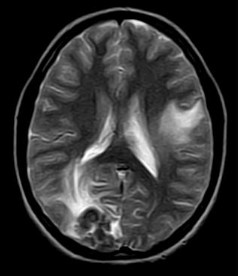

There is a conglomeration of lesions in the right temporo-parieto-occipital and left frontal lobes. These are hypointense on the T2W images and reveal a whorl or bunch of grapes type of enhancement. Note is made of perilesional edema.

On plain MRI, granulomas usually appear isointense to gray matter on the T1W images and may have a slightly hyperintense rim (probably due to the presence of paramagnetic substances). On T2W images, the tuberculomas exhibit variable signal. They are often isointense or hypointense to brain parenchyma and it is postulated that this relative hypointensity is related to T2 shortening by paramagnetic free radicals produced by macrophages, which are heterogeneously distributed throughout the caseous granuloma. The diminished signal on T2W images may also be due to the mature tuberculoma being of greater cellular density than brain. Granulomas may also be hyperintense to brain on T2-weighted images; this is likely due to a greater degree of central liquefactive necrosis in these lesions. Edema surrounding tuberculomata is relatively more prominent in the early stages of granuloma formation.